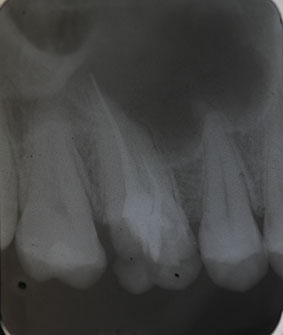

Nach erfolgter Information über die vermutete Prognose unternehmen wir den Versuch, das frakturierte Instrument darzustellen. Nach Entfernung der Aufbaufüllung werden die Kanaleingänge dargestellt (Abb. 2). Es zeigt sich, dass neben dem distovestibulären Kanal auch ein vierter Kanal (mb2) vorhanden ist. Die Darstellung der Wurzelkanaleingänge erfolgt in unserem Haus mit dem Aufsatz 1R des Tigon+. Dank der Abwinkelung des Instruments profitiert man von einer sehr guten Sicht auf die Behandlungsstelle. Zudem erlaubt es ein schnelles und gezieltes Abtragen von Dentin, ohne dabei den Zahn unnötig zu schwächen.

Nach Darstellung aller Wurzelkanaleingänge wird in einem zweiten Schritt das frakturierte Wurzelkanalinstrument dargestellt (Abb. 3 u. 4). Hierfür verwenden wir den Aufsatz 3E des Tigon+. Durch die schmale und lange Form des Instruments erreichen wir einen tiefen und schmalen Zugang.